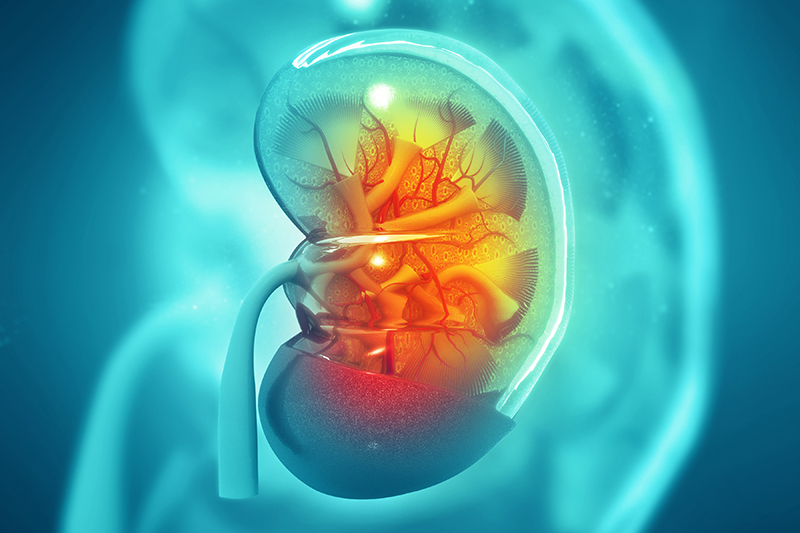

Wissenswertes über Nieren und Harnleiter

Die beiden Nieren (Renes) sind unsere Organe für die Harnproduktion. Über den Harn werden verschiedene Stoffe ausgeschieden, darunter auch giftige Substanzen. Die Nieren unterliegen einer sehr feinen Regulation, was wichtig ist, um zum Beispiel unseren Wasserhaushalt konstant zu halten.

Um Stoffe auszuscheiden, wird das Blut durch einen Filter (Glomerulus) geleitet. Danach werden in einem Labyrinth aus feinen Schläuchen der Grossteil des Wassers und andere Substanzen wieder aufgenommen (rückresorbiert).